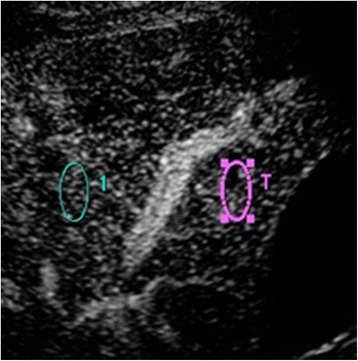

All US examinations were performed with a diagnostic ultrasound system (TUS-A500; Toshiba, Tokyo, Japan) equipped with a 3.75-MHz transducer. No special patient preparations were undertaken. Gray-scale US was performed within 10 min in all patients. Sonazoid™ was injected intravenously (bolus, 0.015 mL/kg) followed by 10 mL of saline within 10 s. The gallbladder and liver parenchyma adjacent to the gallbladder were then scanned through the intercostal view using harmonic imaging with a low mechanical index (0.2–0.3) by one gastroenterologist (J.H.) with 21 years of experience in US. The raw imaging data, from the injection of the contrast medium to the beginning of enhancement of the main portal vein, were stored. Another physician (R.K.), with 3 years of experience in US, who was blinded to all clinical information then analyzed the data and constructed the time-intensity curve (Fig. 1a, b). To construct the time-intensity curve, the major axis of the region of interest (ROI) was set in segment 5 (the liver parenchyma adjacent to the gallbladder), and the control ROI was set in segment 8 on the same image (Fig. 2). The two ROIs were placed at the same depth. Neither ROI included relatively large vessels detectable by CEUS. The intensity ratio (IR) was defined as the peak intensity of segment 5 divided by the simultaneous value of segment 8. We considered that the IR would be suitable to demonstrate increased enhancement of the adjacent liver parenchyma by comparison with another point at the same depth that could be investigated simultaneously under the same conditions.

Fig. 2.

Region of interest (ROI) for two points. A pericholecystic point (red circle, segment 5) and another point at the same depth (blue circle, segment 8), avoiding the large vessels